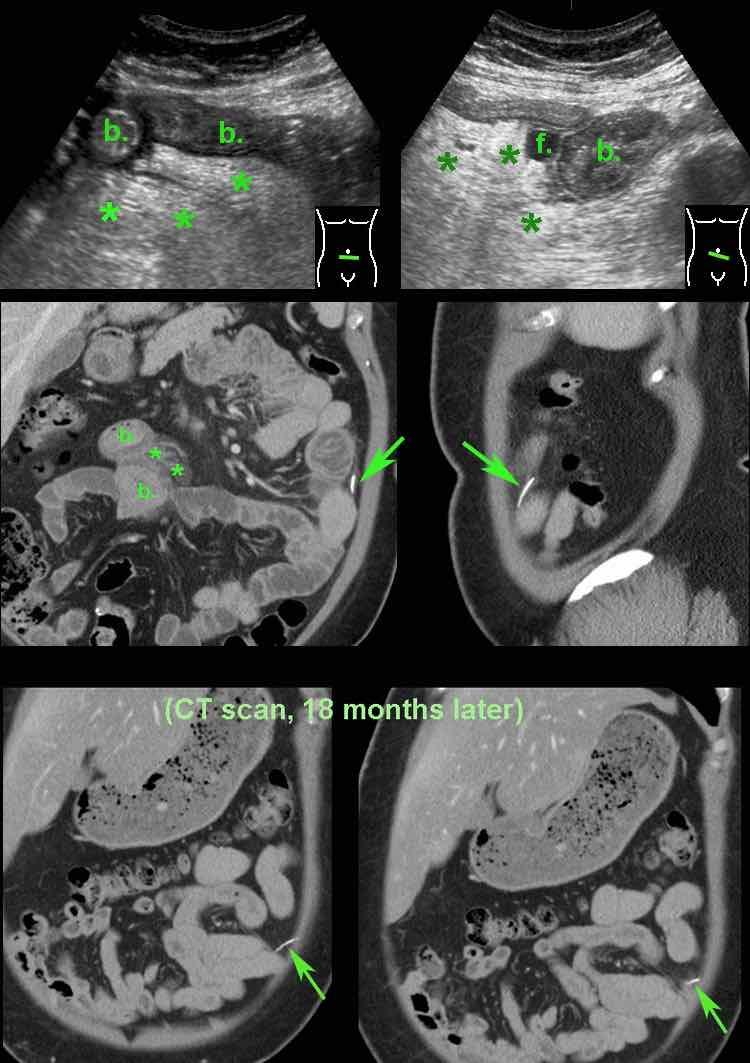

Bệnh nhân nữ 48 tuổi này nhập viện với đau quanh rốn dữ dội kéo dài 12 giờ (Xét nghiệm: bạch cầu 15, CRP 7).

Ngày hôm sau cơn đau giảm, nhưng CRP tăng lên 65.

Siêu âm vùng quanh rốn cho thấy dày thành ruột non (b.) dạng phù nề với nhu động bình thường.

Có một ổ dịch nhỏ (f.) và viêm mạc treo ruột tăng âm, không nén được (*).

CT tiếp theo xác nhận dày thành ruột non (b.) và thâm nhiễm mỡ (*) trong mạc treo ruột. Ở rãnh cạnh đại tràng trái, phát hiện một xương cá (mũi tên).

Rõ ràng xương cá, sau khi xuyên thủng hỗng tràng, đã di chuyển đến vị trí đó.

Thăm dò nội soi ổ bụng tiếp theo không thể xác định được xương cá.

Bệnh nhân hồi phục tốt với kháng sinh.

CT thực hiện vì lý do khác 18 tháng sau cho thấy xương cá di chuyển nhẹ, rõ ràng đã được bao bọc tốt.

Bệnh nhân vẫn ổn định tám năm sau.